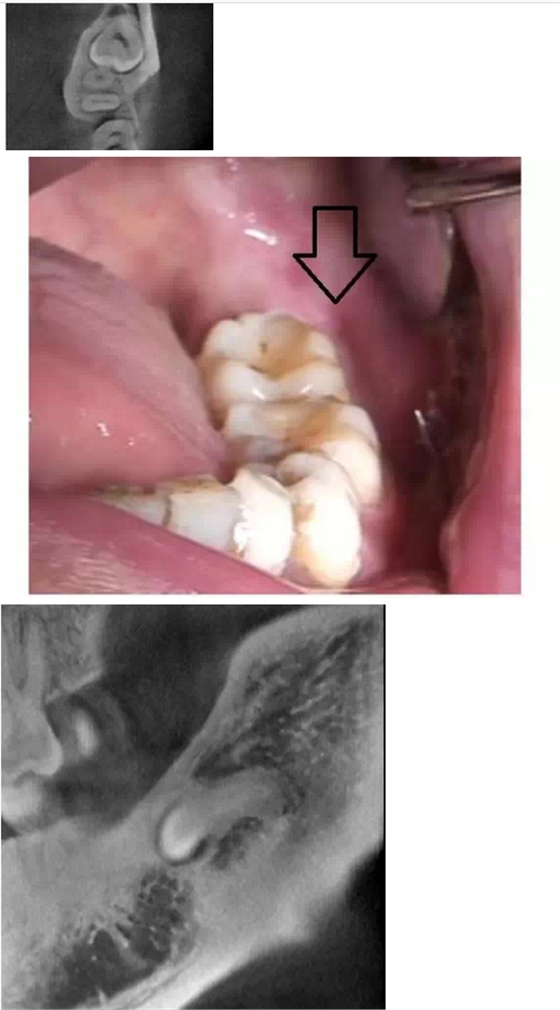

在拔牙一月后,鳥槍換大炮,診所引進(jìn)了三維CT,左側(cè)智齒在拍了CT后,前后頰舌上下關(guān)系就一目了然,此牙更難拔除,因?yàn)橥耆穹▓D二),其上面覆蓋有3mm厚的牙槽骨,其下緣與下牙槽神經(jīng)管緊緊相連,較危險(xiǎn);牙冠前緣與第二磨牙遠(yuǎn)中根也緊緊相連,后緣牙根向上翹;整個(gè)牙齒偏頰側(cè),頰側(cè)皮質(zhì)骨板較厚(圖三),舌側(cè)骨板也較厚,測好牙冠頸部上下距離約為9.5mm。

我們掌握了全方位的信息后,藉著CT向患者講解該牙齒的情況,患者充分理解拔牙的風(fēng)險(xiǎn)和醫(yī)生所需要的經(jīng)驗(yàn)和勇氣。因著有CT,術(shù)前的準(zhǔn)備更加充分:手術(shù)切口的設(shè)計(jì)和種植機(jī)去骨的部位選擇均在第二磨牙的遠(yuǎn)中頰側(cè)(圖四);車針長度的定位在9mm,防止磨到神經(jīng)管;掌握了牙根根尖部分是彎向下(圖五),就可以評(píng)估常規(guī)的挺子是很難進(jìn)去的,特別設(shè)計(jì)了四把不同角度的挺子。整個(gè)拔牙過程非常順利,行云流水,均在我們的掌握之中,猶如四驅(qū)的牧馬,人雖行駛在惡劣的沙漠地,仍是馳騁疆場,酣暢淋漓。

第二顆智齒在CT的輔助下整個(gè)拔除時(shí)間比第一顆減少了一小時(shí),而且創(chuàng)口?。▓D六),術(shù)后反應(yīng)輕,患者在拔除的第二天胸悶的感覺就慢慢消失。